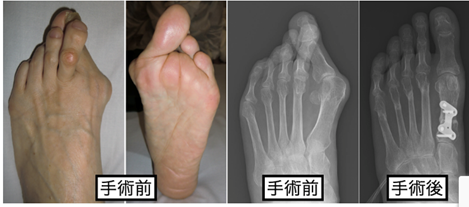

昔からある方法は切除関節形成術です。関節が重度に破壊されている場合に選択される手術です。

- ホフマン法など: 重度の変形や痛みを伴う場合に、中足趾節(MTP)関節の骨の一部を切除して痛みを和らげ、歩行機能を改善します。

最近は関節温存手術が施行されることも多いです。生物学的製剤など、RAの薬物治療の進歩により関節破壊の進行が抑制されるようになったため、関節を温存する手術が増加しています。

骨切り術: 骨の一部を切って形を整えることで、関節を温存し、足趾のアライメントを改善します。